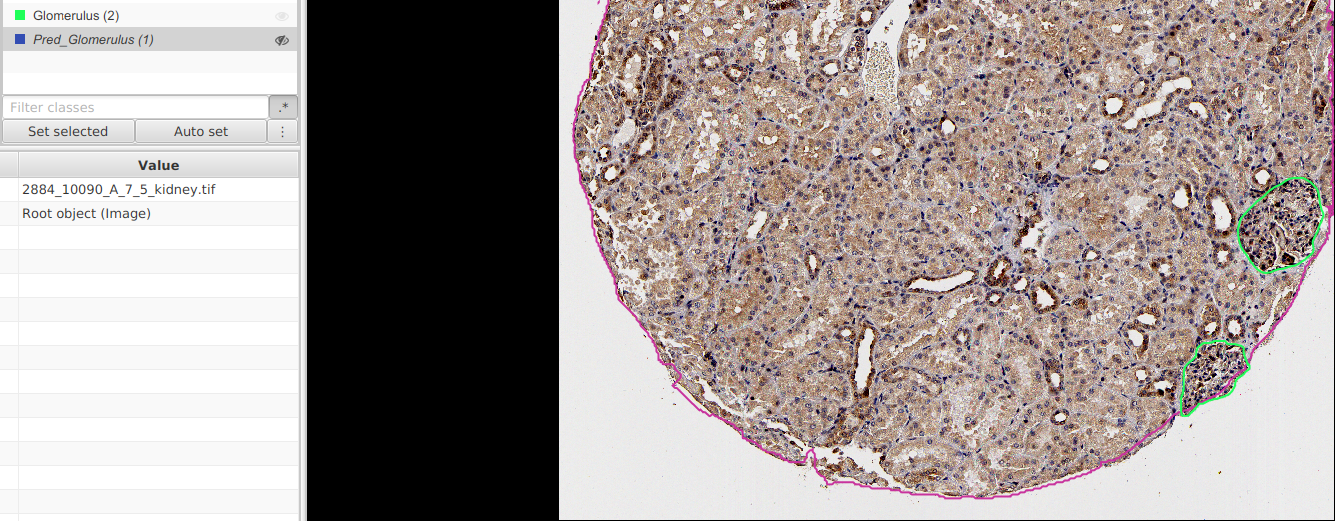

- Click "Run" for one image to verify that GT annotations are imported correctly.

"more options" next to "Run" and choose "Run for project" to import GT on all selected images. - Keep the imported GT class name (for example

Glomerulus) and reuse this exact name asgt_classin steps B and C. - If one structure is split across several polygons, merge these polygons before continuing.

def gt_class = "Glomerulus"

def pred_class = "Pred_Target"

def inter_class = "Inter_Target"

def union_class = "Union_Target"

- Check in the annotations list that

Inter_TargetandUnion_Targetwere created.